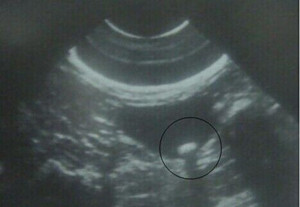

1、 B超检查:是肝胆系结石极常见的检查方法,其目的在于:诊断肝胆系结石、了解结石引起的胆囊损害、查找某些结石的病因;其优点是方便、快捷、无损伤。